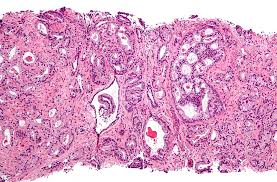

What Are The Symptoms Of Advanced Prostate Cancer - Imaging Diagnosis And Follow Up Of Advanced Prostate Cancer Clinical Perspectives And State Of The Art Radiology / Stage 1 is the least advanced form of prostate cancer.. With advanced disease, mainly if you have not had treatment to the prostate itself, you may have problems passing urine or see blood in your urine. Other common side effects include fatigue,. Pain in the bones of those areas. The prognosis for prostate cancer with bone metastases depends on several factors. Advanced prostate cancer, also called metastatic cancer, means the cancer has spread to other areas of your body.

Advanced Prostate Cancer North Texas Prostate Cancer Coalition from www.ntxpcacoalition.org If it's in your pelvic bones, you may have. Symptoms of advanced prostate cancer. Men with advanced prostate cancer usually feel pain in the areas it has spread to. The urethra passes through the center of the gland from the bladder to the penis. It's characterized by a psa of less than 10 ng/ml, a grade group. If you are concerned about having one of these types of advanced prostate cancer, you may want to know what are the symptoms to look after. Prostate cancer may cause no signs or symptoms in its early stages. If you have advanced prostate cancer and are approaching the end of your life, you might have a lot of questions about what will happen.

If it's in your pelvic bones, you may have. Advanced prostate cancer means that a cancer that began in the prostate gland has spread to another part of the body. It also can help you feel better and live longer. When prostate cancer spreads to the bones, it's stage 4, an advanced stage. Dull, deep pain or stiffness in your pelvis, lower back, ribs, or upper thighs; The urethra passes through the center of the gland from the bladder to the penis. Symptoms for advanced prostate cancer can be hard to cope with. If you are experiencing pain, then there are ways to relieve or reduce the same. Decreased force in the stream of urine. Symptoms depend on the size of new growth and where the cancer has spread in the body. Answer you may have no symptoms with advanced prostate cancer. Metastatic prostate cancer symptoms vary greatly depending on the level of the disease, sidana says. Symptoms of advanced prostate cancer can include bone pain, problems passing urine and tiredness.